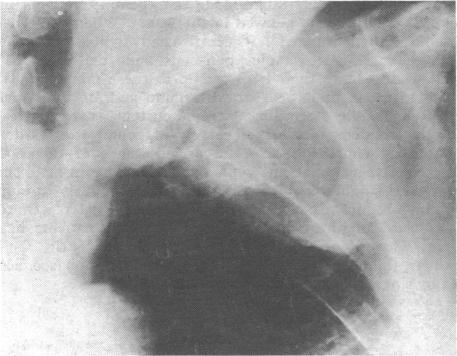

Myeloma presenting with Pancoast's syndrome.